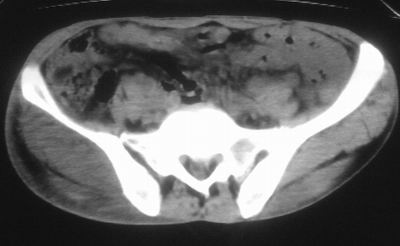

患者,男,63岁,自诉3个月前发现右臀部包块,触及疼痛,治疗后缩小。前天突然增大。无高热病史。

给个骨窗,判断一下肿块是否与髂骨有关,肿块内出血是肯定的,至于是感染形成的脓肿还是起源于肌肉或纤维组织的肉瘤则难以确定,不过从影像上看,包膜完整,且环形增厚,病灶下部见斑片状底密度坏死,个人倾向感染可能性大

肌间隙明显混浊,三个月前治疗有缩小,支持考虑臀大肌下脓肿伴出血,肿瘤如果出现瘤内出血的话瘤外边界应该较清楚,现在表现为一种恶性征像,但骨质无明显异常,且臀小肌边界清楚,不符合恶性表现.